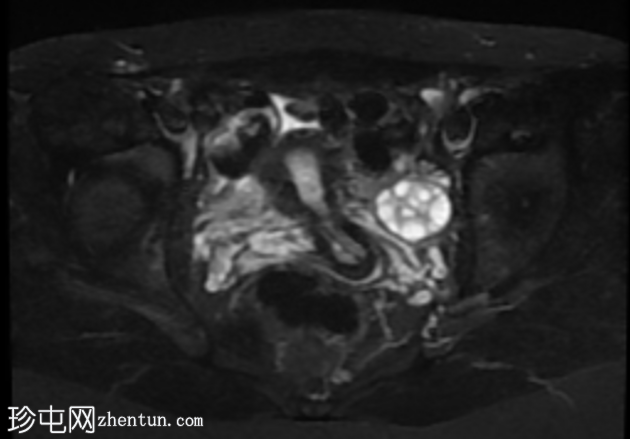

轴位

T2加权像

子宫前倾位,分区解剖结构正常。矢状位序列可见子宫前壁肌层局灶性边界不清的低信号病灶,但在后续序列中未见明显,符合短暂的生理性子宫肌层收缩表现。

双侧卵巢大小及卵泡活动均正常。未见囊性或实性肿块。

腹部MRI检查结果正常。